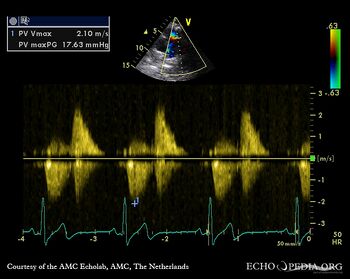

Severe pulmonary regurgitation

PSAX: Color Doppler, severe pulmonary regurgitation Continuous-wave signal of transpulmonary flow